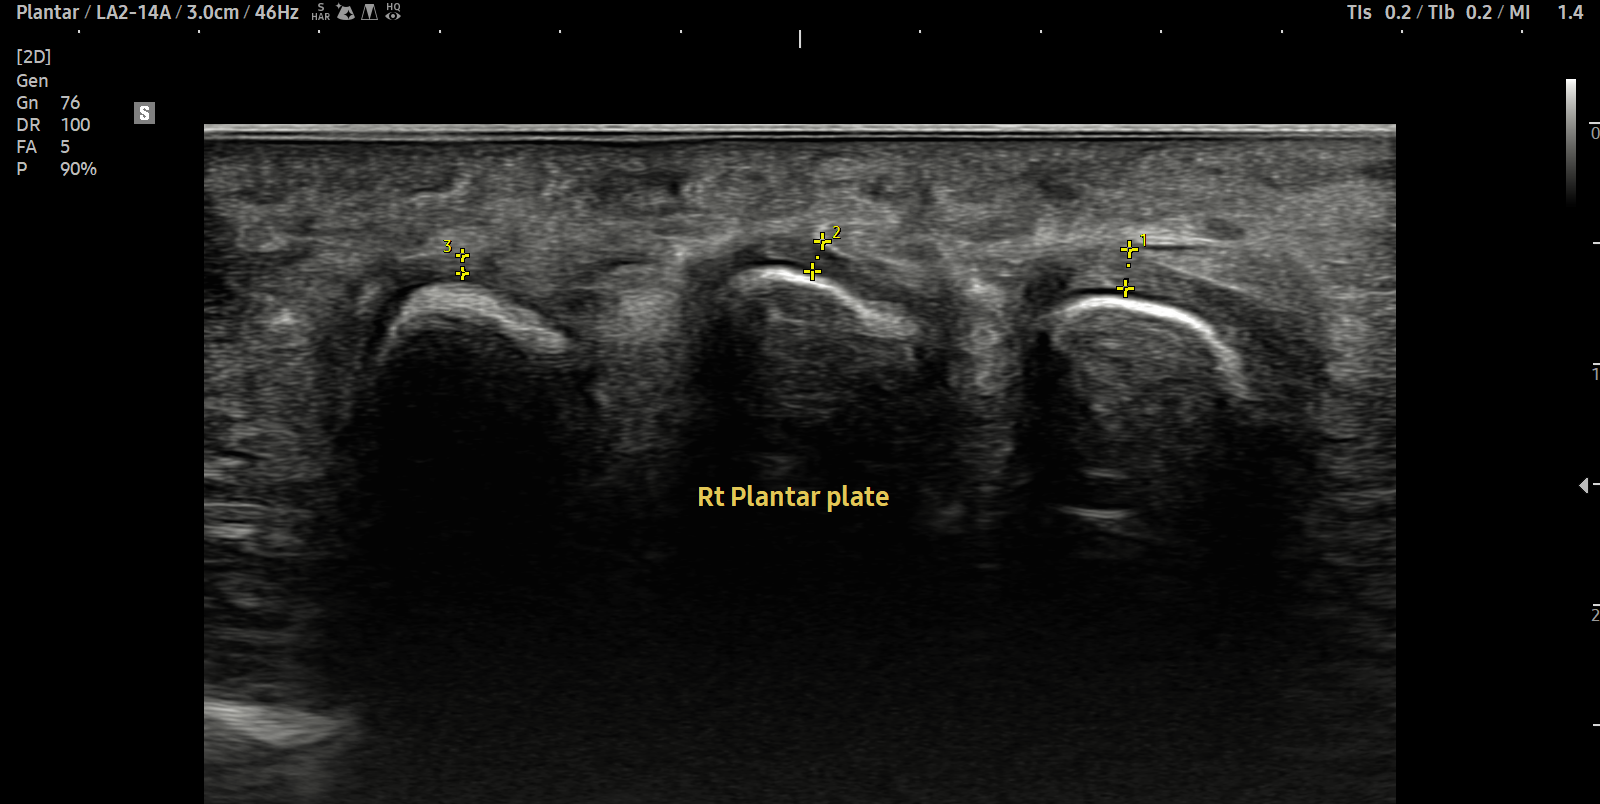

- 치료기간 : 2025. 5. 1. ~ 2025. 6. 14

- 치료횟수 : 10 회

[치료 전]

[치료 후]